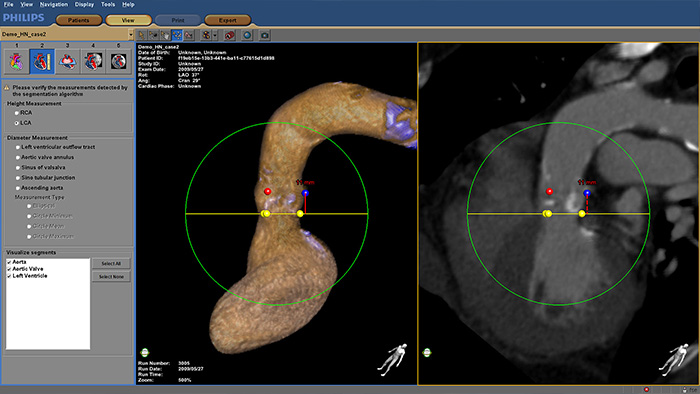

Boostez la confiance et l'aisance pendant le remplacement de la valve aortique par cathéter (TAVR) et d'autres procédures SHD difficiles. L'expérience utilisateur immersive est hautement automatisée pour simplifier la planification, la sélection du dispositif et la sélection de l'angle de projection. Pendant les procédures, il fournit un guidage d'image en direct pour soutenir le positionnement du dispositif.